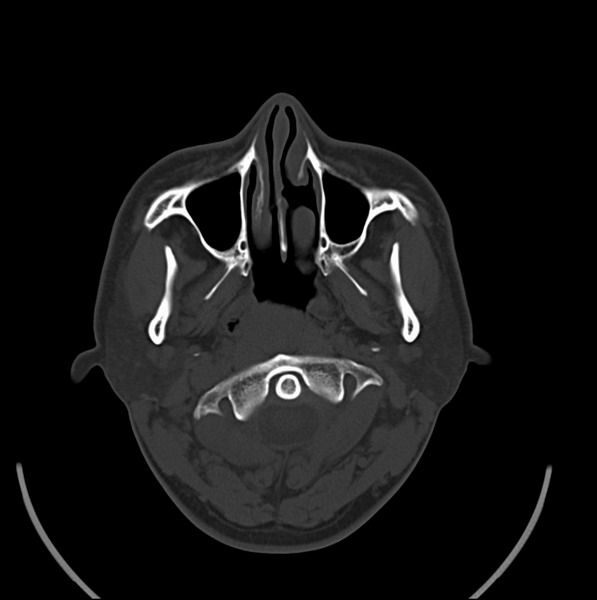

扫描示鼻咽腔不对称,中度狭窄,右侧咽隐窝消失,局部软组织肿块,鼻咽右侧壁增厚形成肿块,突入鼻咽腔,肿块平扫呈等密度,肿块向深部侵润,右侧翼内外肌受侵,右侧咽旁间隙变窄;向后生长,头长肌界线欠清,向后上生长侵犯同侧颈动脉鞘区。双侧海绵窦增宽,内见软组织影与鼻咽部肿块相连。考虑鼻咽癌。鼻咽癌主要是放射治疗,且效果较好;到当地有治疗设备较大医院治疗即可。

这个病例有点特殊,和常见的鼻咽癌不太一样,以向颅内侵犯为主,骨质破坏区小。鼻咽癌首先要考虑,有没有其他可能?本人不会看mr片,期待有人能讲解,期待病理。

建议强化检查,鼻咽部纤维血管瘤待排。

鼻咽部新生物(纤维血管瘤?鼻咽癌?)侵犯右侧中颅窝底及右侧海绵窦;建议必要时活检定性。

鼻咽部新生物侵犯右侧中颅窝底及右侧海绵窦,鼻咽癌可能性大。建议增强扫描。纤维血管瘤禁忌穿刺。